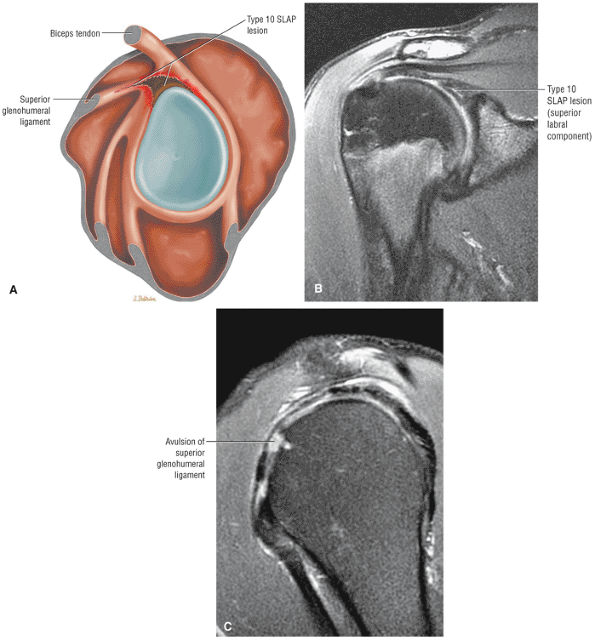

The imaging reference to hypertrophy of the coracoacromial ligament correlates with fraying or fragmentation of the ligament in association with impingement.

-

A symptomatic os acromiale is associated with marrow edema on either side of the synchondrosis.

Degenerative tendinopathy or intrinsic tendon degeneration associated with eccentric tensile overload may be the primary pathology in impingement.